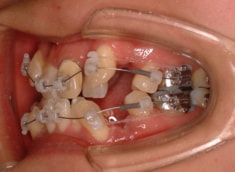

治療開始時

治療開始から約1年後